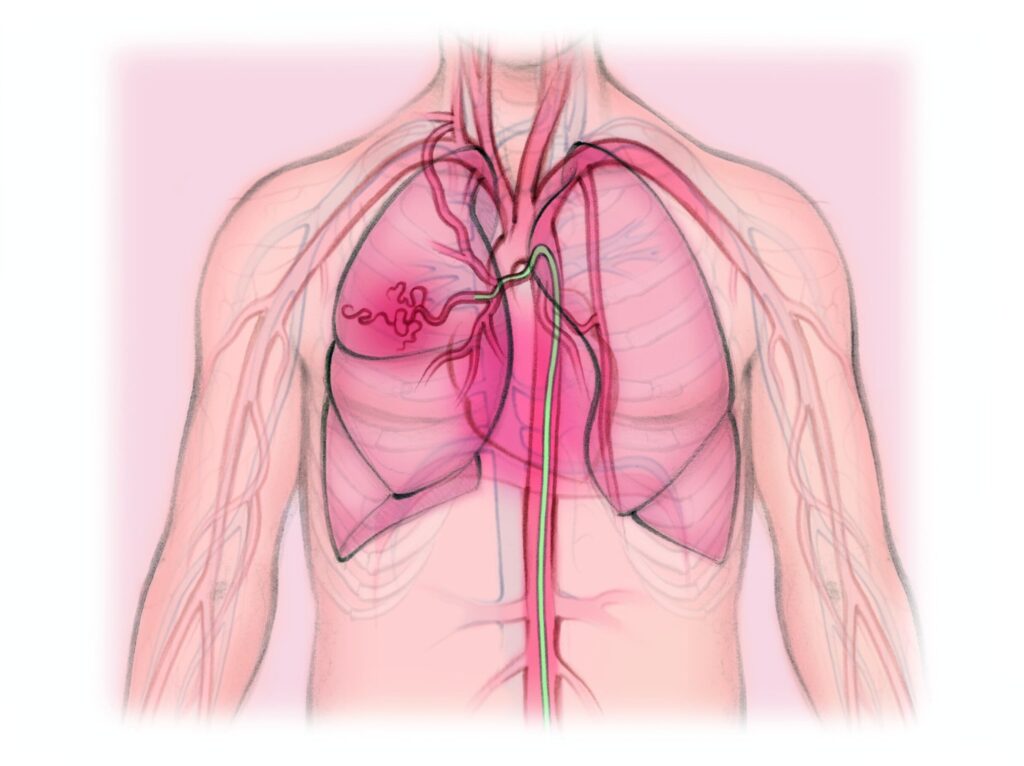

Embolización de las arterias bronquiales

¿Una alternativa para el manejo de la hemoptisis masiva? La hemoptisis masiva ha sido definida en forma arbitraria como la...